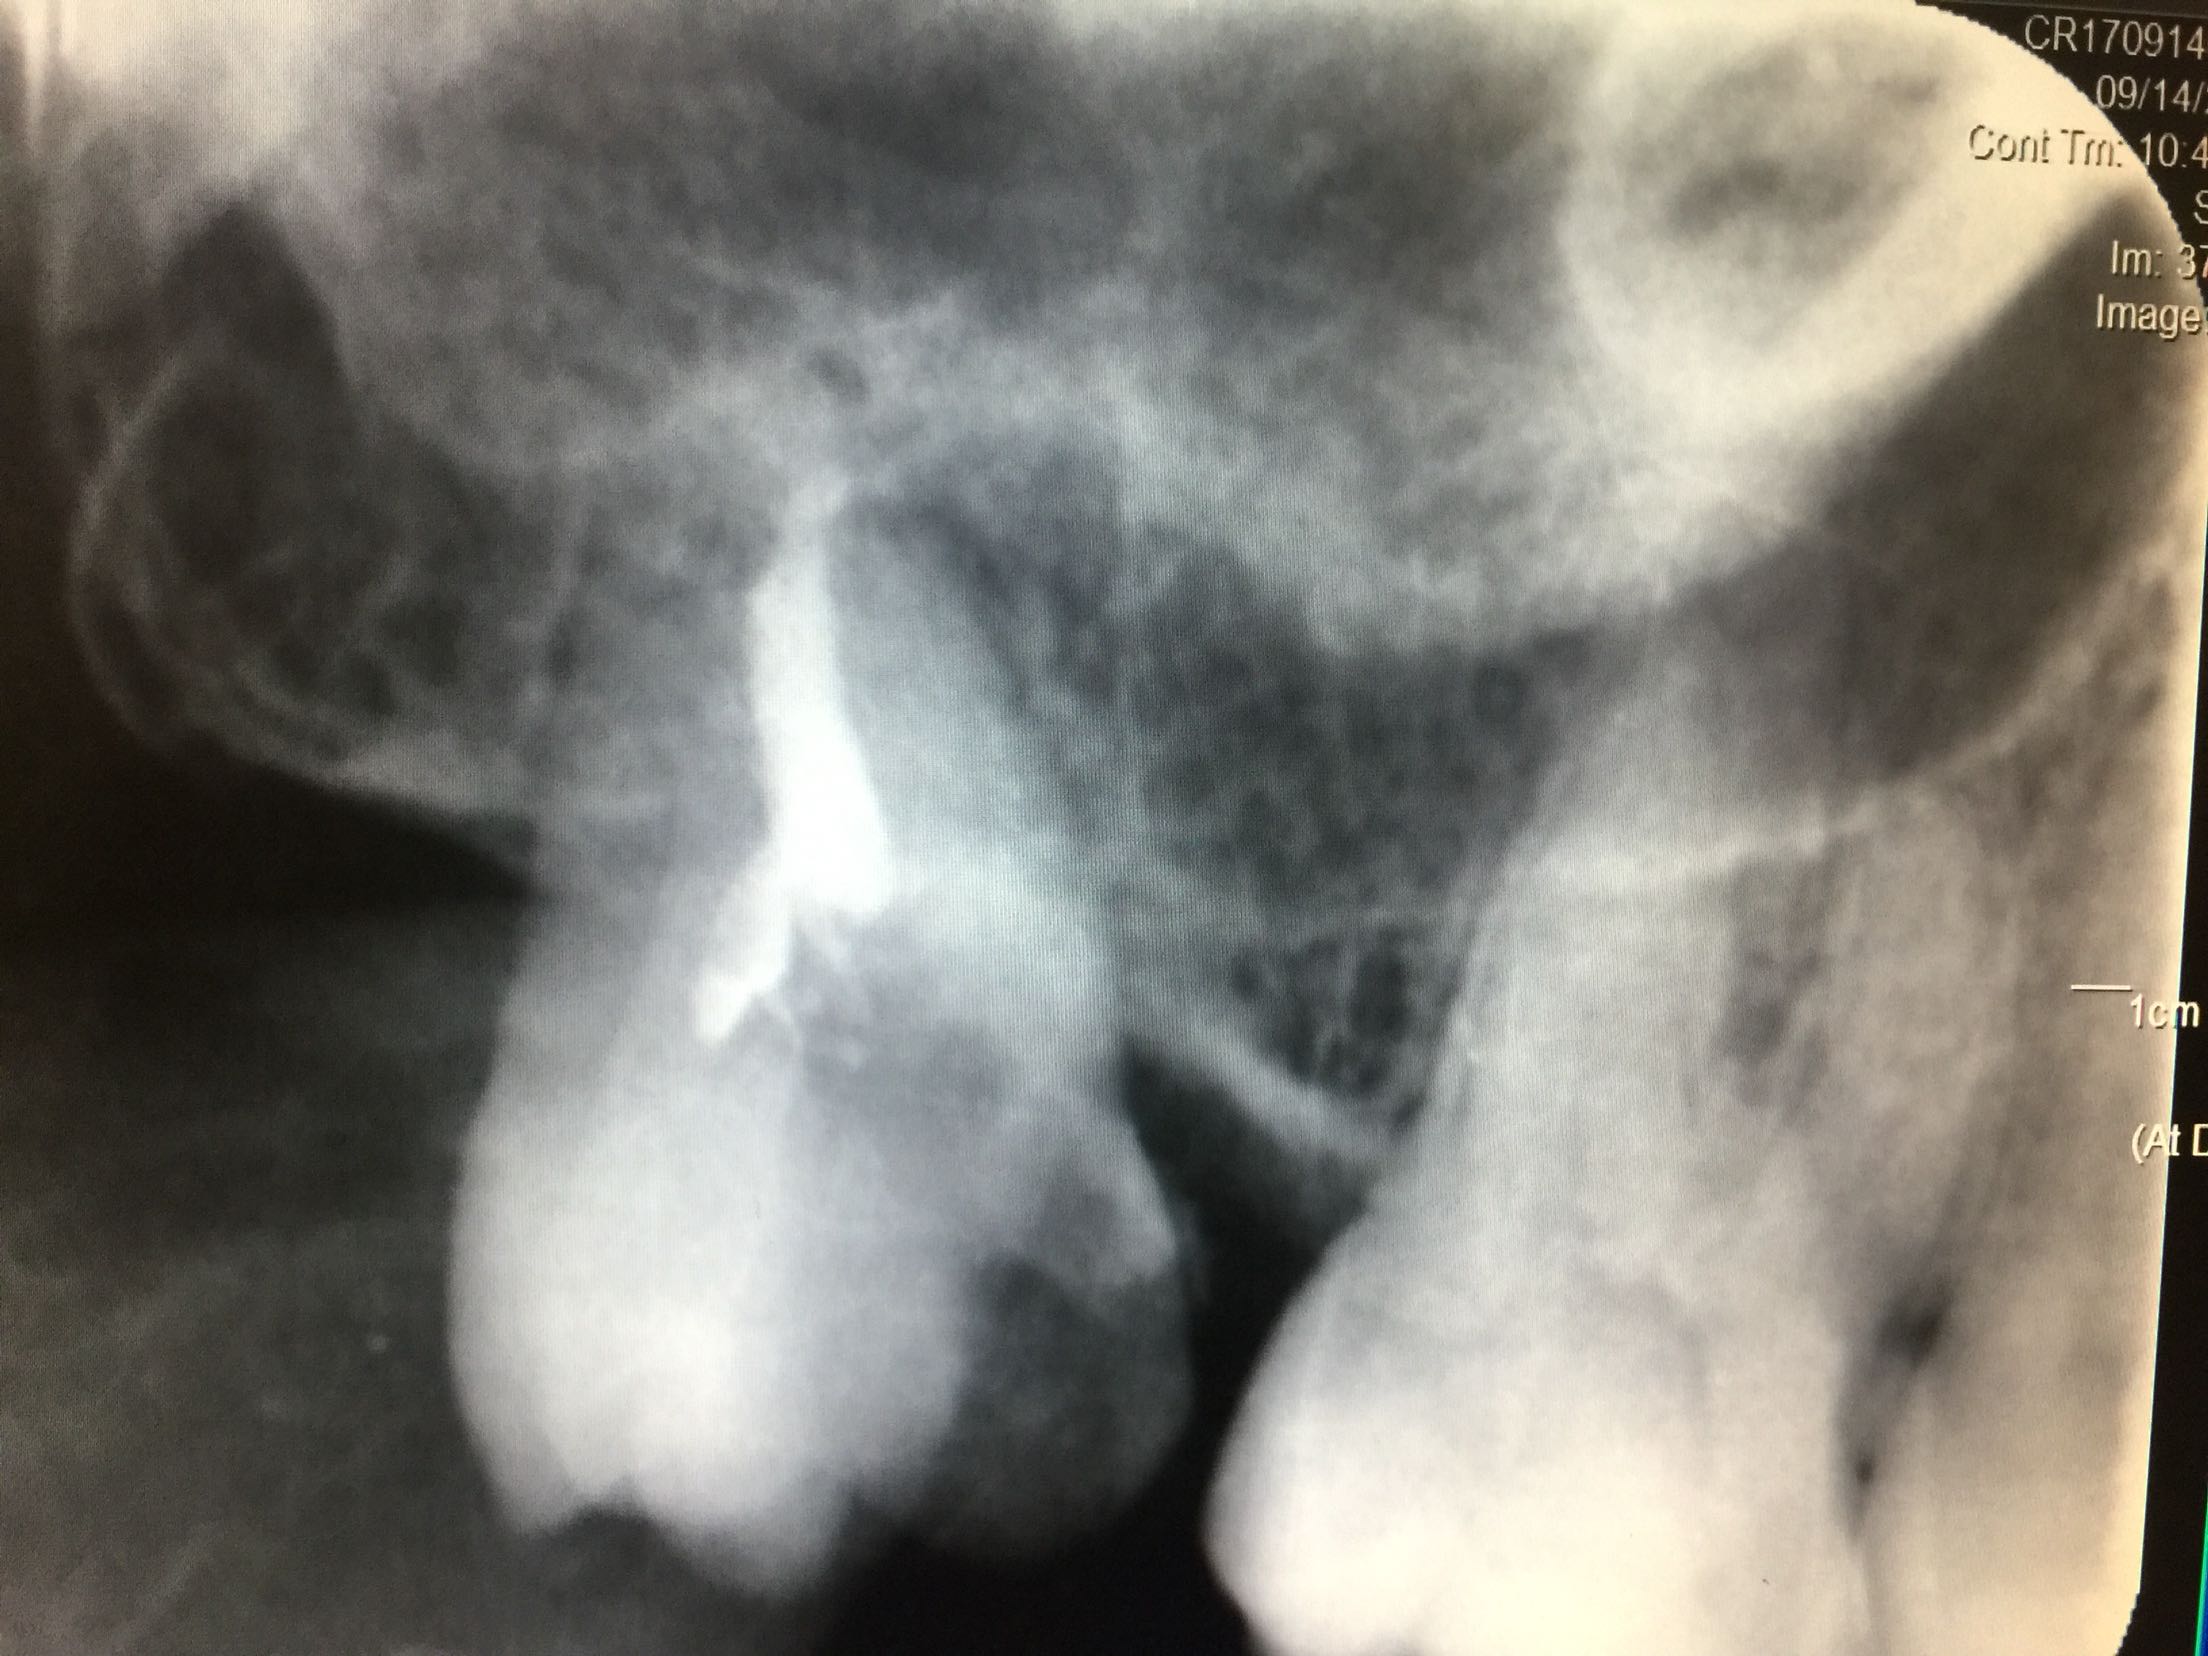

检查:全口卫生尚可,牙石+,软垢+,牙龈正常。18牙近中倾斜,近中邻合面龋,内有大量软龋,深达牙本质深层,已累及髓腔,冷+,探-,叩-,松-。颊侧牙龈未见异常。 17牙缺失,缺牙间隙小,无明显骨尖,对合牙无伸长。 X线:18牙近中邻合面可见龋坏,累及髓腔,未行根管治疗,根尖区未见暗影,牙槽骨吸收至颈部1/3。

诊断:18牙牙髓炎 17牙牙列缺损 治疗计划:因17牙缺牙间隙小,暂不行修复 18牙行去髓术 治疗:碧蓝麻局部浸润,18牙去净龋坏,开髓揭髓顶,探查根管1根,牙髓摘除术,k挫初步预备,根管测长仪测量根管长度,各根管内导入根管润滑剂EDTA,Protaper镊钛器械预备根管,冲洗,超声荡洗,水溶性氢氧化钙充填根管,暂封,约复诊。 一周后复诊 诊间无不适,18牙暂封完好,冷-,探-,叩-,松-。 试主尖,

大锥度牙胶尖+AH-PLUS糊剂充填根管,热压充填牙胶,暂封。树脂充填。